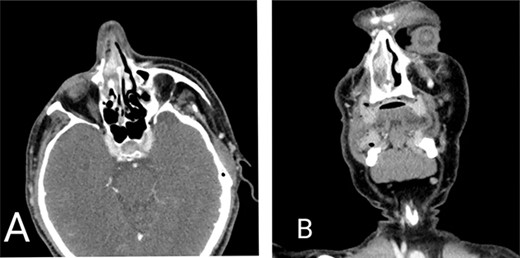

A 59-year-old male with a history of intermittent epistaxis of 20-day duration presented with active bleeding from his right nostril, which was refractory to compression; we applied nasal packing with adrenaline, with only minimal improvement. Physical examination revealed a red-purple mass lesion obstructing the right nasal passage. A computed tomography scan showed a mass in the right nasal cavity attached to the septum measuring 1 × 1.5 cm, shown in Figure 1. Therefore, urgent complete surgical excision through functional endoscopic sinus surgery was done, besides sphenopalatine artery ligation, with no complications.

Computed tomography scan of the head. (A) Axial view and (B) coronal view demonstrating mass lesion in the right nasal cavity attached to the septum measuring 1 × 1.5 cm.